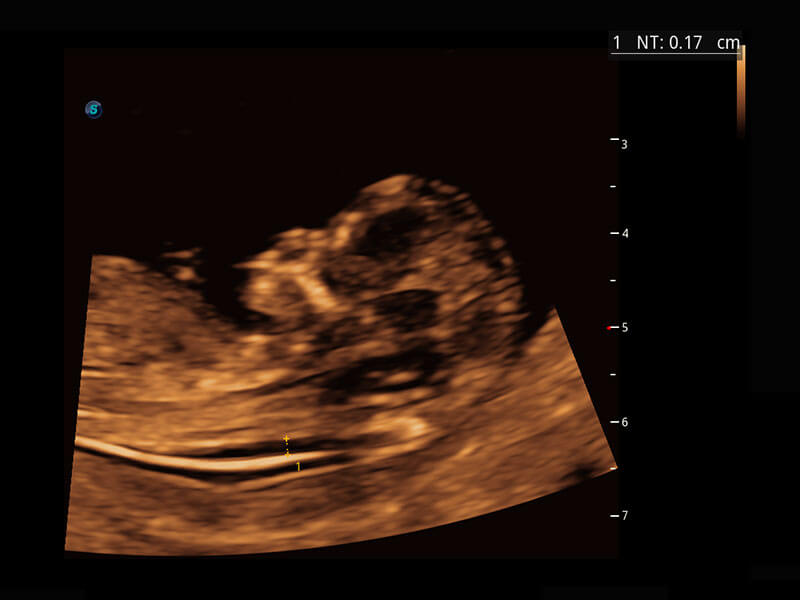

P60在胎儿早孕期超声筛查中为您带来优异的图像质量。

早孕-胎心

P60搭载一系列胎儿心脏成像技术,实现精细的胎儿心脏评估。